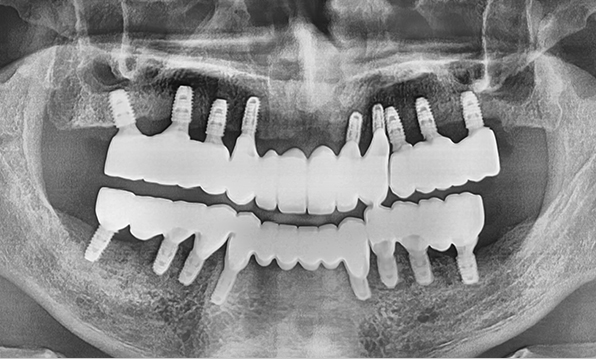

Minimal PlacementUsing a method of placing 6–7 implants in the maxilla and 6 in the mandible, this approach restores both posterior and anterior teeth, efficiently rehabilitating the entire oral cavity.

Before & After

| Before | After |